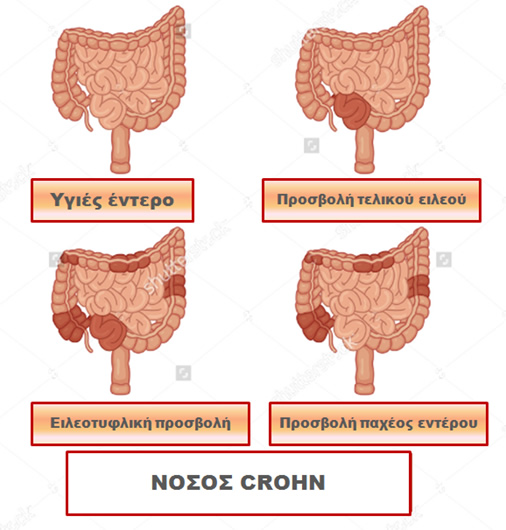

Η νόσος Crohn περιγράφηκε για πρώτη φορά το 1932 από τον Burrill Β. Crohn και τους συνεργάτες του στο Νοσοκομείο Mount Sinai της Νέας Υόρκης. Οι ασθενείς με νόσο Crohn έχουν μία εφόρου ζωής φλεγμονή του γαστρεντερικού σωλήνα, η οποία ξεκινά από την εσωτερική επένδυση του τοιχώματος του, που είναι γνωστή ως βλεννογόνος, και, συνήθως επεκτείνεται και στα βαθύτερα στρώματα του. Η περιοχή στην οποία πιο συχνά αναπτύσσεται η φλεγμονή είναι το σημείο της ένωσης του λεπτού με το παχύ έντερο, δηλαδή εκεί που ο τελικός ειλεός, το τελευταίο τμήμα του λεπτού εντέρου, ενώνεται με το πρώτο τμήμα του παχέος εντέρου, που ονομάζεται τυφλό.

Ωστόσο, η νόσος Crohn μπορεί να εμφανισθεί σε οποιοδήποτε σημείο της εντερικής οδού, δηλαδή από τη στοματική κοιλότητα έως τον πρωκτό και μπορεί να επηρεάσει μία ή και περισσότερες περιοχές. Δεν υπάρχει τρόπος να προβλέψουμε ποιος και πότε θα αναπτύξει τη νόσο Crohn. Πρόκειται για μία χρόνια νόσο που μπορεί να εμφανισθεί ανά πάσα στιγμή, μπορεί να υφεθεί χωρίς εξήγηση και μπορεί να ξαναπαρουσιασθεί έντονα χωρίς προφανή αιτία.

Ως επί το πλείστον η νόσος του Crohn εμφανίζεται είτε στο λεπτό ή/ και στο παχύ έντερο, είτε στην ορθοπρωκτική περιοχή, ή, ακόμη και στις δύο.

Είτε γίνει «ανοικτά» είτε λαπαροσκοπικά, η χειρουργική επέμβαση κοιλίας πραγματοποιείται για να αντιμετωπίσει το πάσχον τμήμα του εντέρου. Συνήθως, η προβληματική περιοχή εμφανίζει διάτρηση, απόφραξη ή συρίγγιο. Οι δύο πιο κοινές χειρουργικές επεμβάσεις για τη νόσο Crohn είναι η αφαίρεση του τέλους του λεπτού εντέρου και της αρχής του παχέος εντέρου, επέμβαση που ονομάζεται ειλεοτυφλεκτομή, καθώς και η αντιμετώπιση της στένωσης του εντέρου που προκαλεί την απόφραξη, με επεμβάσεις που ονομάζονται εντερεκτομές ή στενωσοπλαστικές. Σε κάθε περίπτωση σκοπός της επέμβασης είναι η διατήρηση όσο το δυνατόν μεγαλύτερου μήκους εντέρου, ώστε να παραμείνει όσο πιο φυσιολογική γίνεται η λειτουργία του πεπτικού σωλήνα που απομένει.